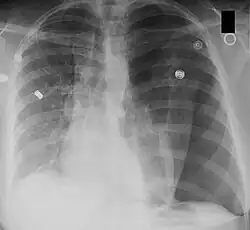

| Left tension pneumothorax with a large, well-demarcated area devoid of lung markings with tracheal deviation and movement of the heart away from the affected side. |

Tension pneumothorax

Tension pneumothorax is an emergent condition in which air gets trapped in the space between the chest wall and the lung. This space is referred to as the pleural space. Because air can't escape from this space, the air pocket grows larger and larger, resulting in the lung collapse closest to the pneumothorax. Forces are transmitted to the mediastinum and effectively "push" the mediastinal structures to the opposite side of the chest.[5]